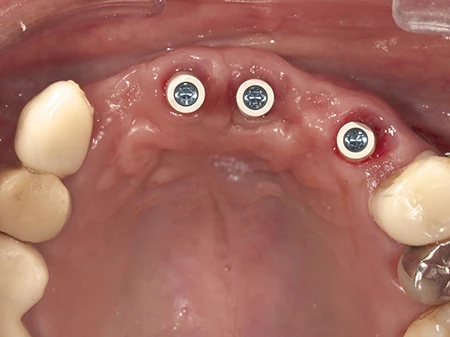

インプラント埋入から2ヶ月後、仮歯を装着します。

最終的な型取りをデジタルスキャンでおこないます。

最終的なジルコニアセラミックが入った状態。